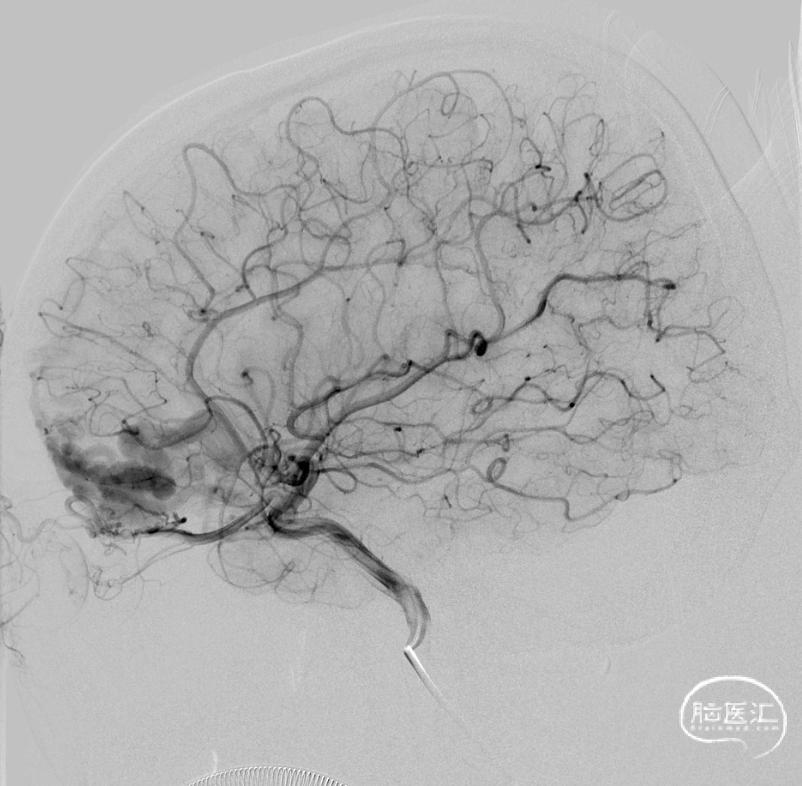

二期治疗